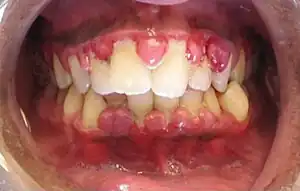

The symptoms of gingivitis are somewhat non-specific and manifest in the gum tissue as the classic signs of inflammation:

- Swollen gums

- Bright red or purple gums

- Gums that are tender or painful to the touch

- Bleeding gums or bleeding after brushing and/or flossing

- Bad breath (halitosis)

Additionally, the stippling that normally exists in the gum tissue of some individuals will often disappear and the gums may appear shiny when the gum tissue becomes swollen and stretched over the inflamed underlying connective tissue. The accumulation may also emit an unpleasant odor. When the gingiva are swollen, the epithelial lining of the gingival crevice becomes ulcerated and the gums will bleed more easily with even gentle brushing, and especially when flossing.

Complications

- Recurrence of gingivitis

- Periodontitis

- Infection or abscess of the gingiva or the jaw bones

- Trench mouth (bacterial infection and ulceration of the gums)

- Swollen lymph nodes